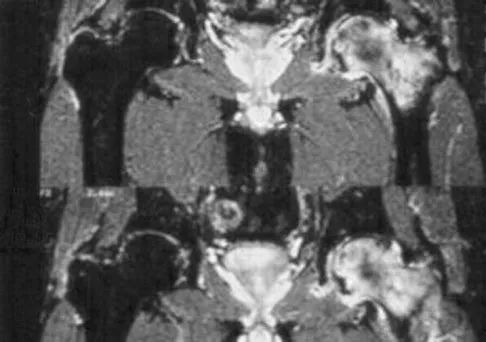

Question 8

A 58-year-old man reports a 2-month onset of groin pain with no history of trauma. Examination reveals that range of motion of the hip is mildly restricted, and he has pain with both weight bearing and at rest. An MRI scan is shown in Figure 20. Treatment should consist of

Explanation